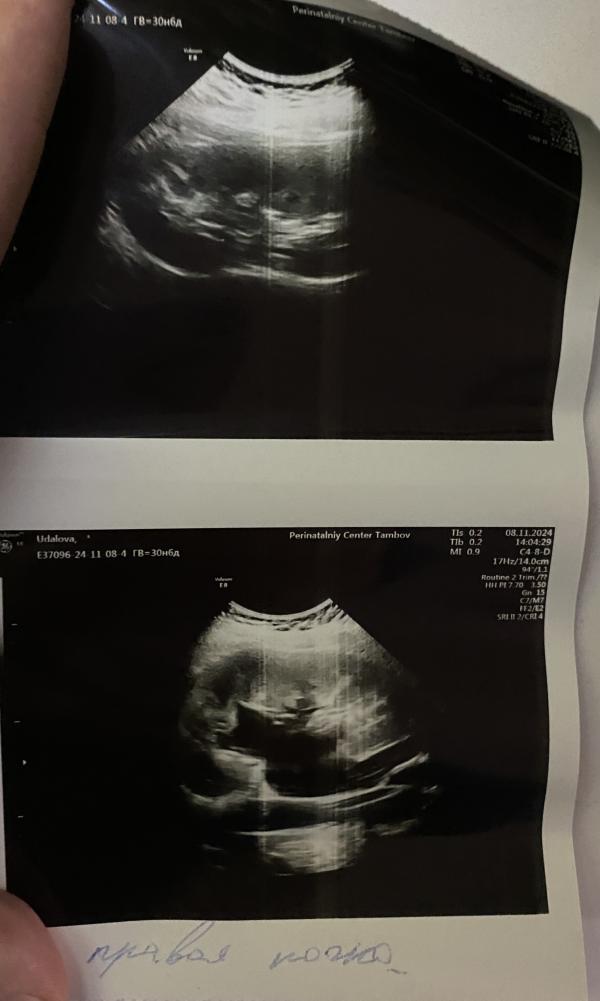

У меня гидронефроз нашли на 36 неделе. 26 мм лоханка, сказали наблюдать колено локтевая поза пить уросборы и часто сдавать мочу. У вас сколько лоханка ? И как она дает знать о себе? Мне просто случайно нашли по узи

@lil_lis, у меня 30 лоханка оказывается 🥲пересмотрела УЗИ, тоже справа. Меня успокоили, сказав что на беременность бывает и именно справа чаще всего. Нужно наблюдать, вставать в эту позу. У вас боли есть? Вы пьете фитодизин? Отеки с утра сверяйте на руках и взвешивайтесь с утра. Думаю их вы не упустите